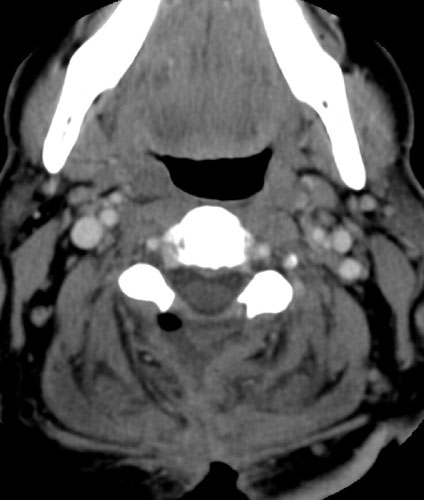

Contrast enhanced axial CT scan  demonstrates unroofing of the spinal canal from the C2 to the C7 with bilateral laminectomies and removal of the spinous processes. There is a fluid collection without significant rim enhancement in the post surgical bed at the C2 level, posterior to the spinal canal. Within this, there is some air. The fluid collection appears to extend inferiorly to the C3 level, and then a small slit of fluid continues inferiorly to the C5 - 6 level (not shown), where it appears to communicate with the midline incision .